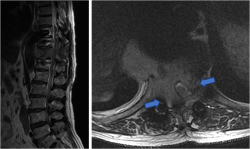

图3-1,CT矢状面和冠状面重建,显示病变为成骨性,病变内有点状钙化。

图3-2,CT横断面显示病变累及L2-L3水平椎骨。

图3-3,MRI矢状面及冠状面显示病变侵入椎管明显压迫硬膜囊和马尾神经

图3-4,MRI横断面显示病变存在软组织成分,在左侧L2-3椎间孔区肿瘤累及椎管内外,明显压迫马尾神经,并且包绕左侧L2神经根。